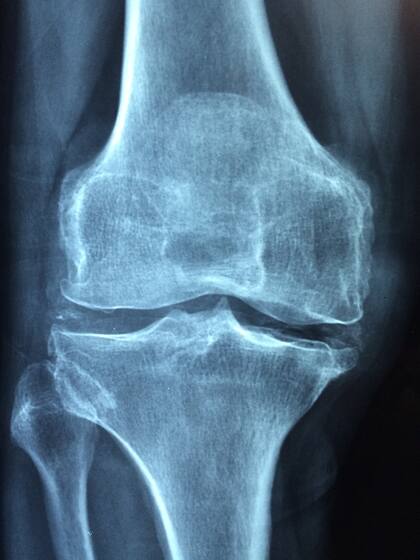

A medida que envejecemos, la producción de colágeno disminuye, lo que puede llevar a un deterioro del cartílago y a aumentar el riesgo de trastornos como la osteoartritis, enfermedad degenerativa de las articulaciones que provoca dolor, hinchazón y rigidez. Las sobrecargas articulares, especialmente comunes en la rodilla, son otra de las dolencias más frecuentes derivadas del desgaste de estos tejidos, y este riesgo aumenta significativamente para los adultos mayores.